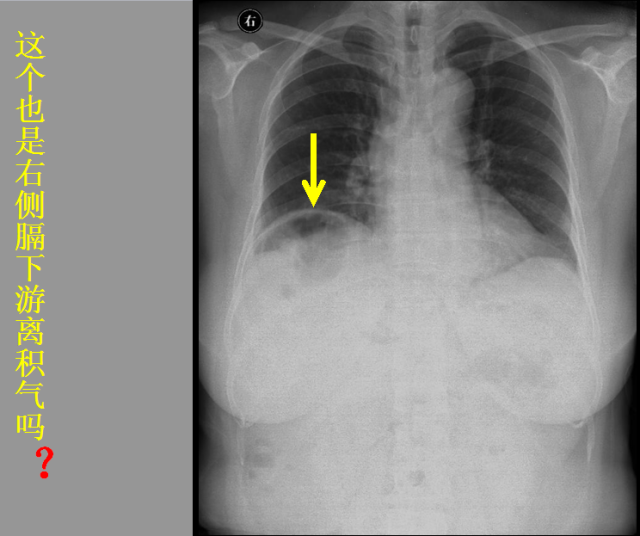

急胸症篇

急腹症篇